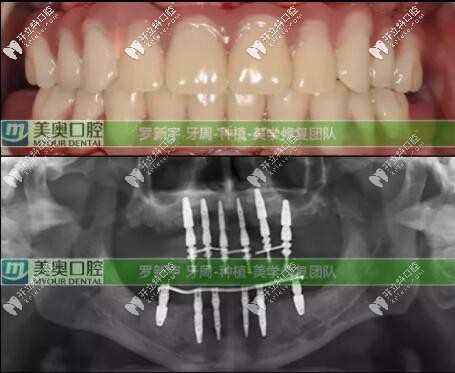

接著就是種植牙修復計劃:根據(jù)臨床上的口腔數(shù)據(jù),根據(jù)顧客的實際情況選擇了Straumann? Pro Arch無牙頜種植修復解決方案,拔除全部松動的余留牙,雖然犧牲可能有點大,但換來的是全口好牙還有自信。

全口即刻負重種植就是:在當天種植并完成臨時修復,PS:臨時修復是指臨時牙冠。為患者帶上臨時牙,可實現(xiàn)當天吃蘋果的愿望。即刻修復就是這么快。后期又進行了為期六個月的復診和跟蹤治療;

六個月后口腔檢查評價:種植體全部存留、臨時修復體存留、終末修復體(長久性的牙冠)存留;可以說這次種植修復是很成功的。